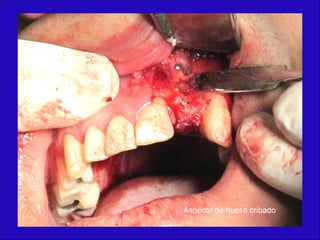

Múltiples perforaciones en hueso compacto

Aspecto de hueso cribado

La conformación quirúrgica de un contorno alveolar adecuado es

determinante para la correcta aplicación y aceptación de los implantes

de titanio, aquí proponemos una técinica para lograr el espesor óseo

suficiente y la corrección estética del proceso, ya que antiguamente al

extraer un diente se acostumbraba presionar las tablas alveolares

“para cohibir la hemorragia”, con el colapso subsiguiente de la región.